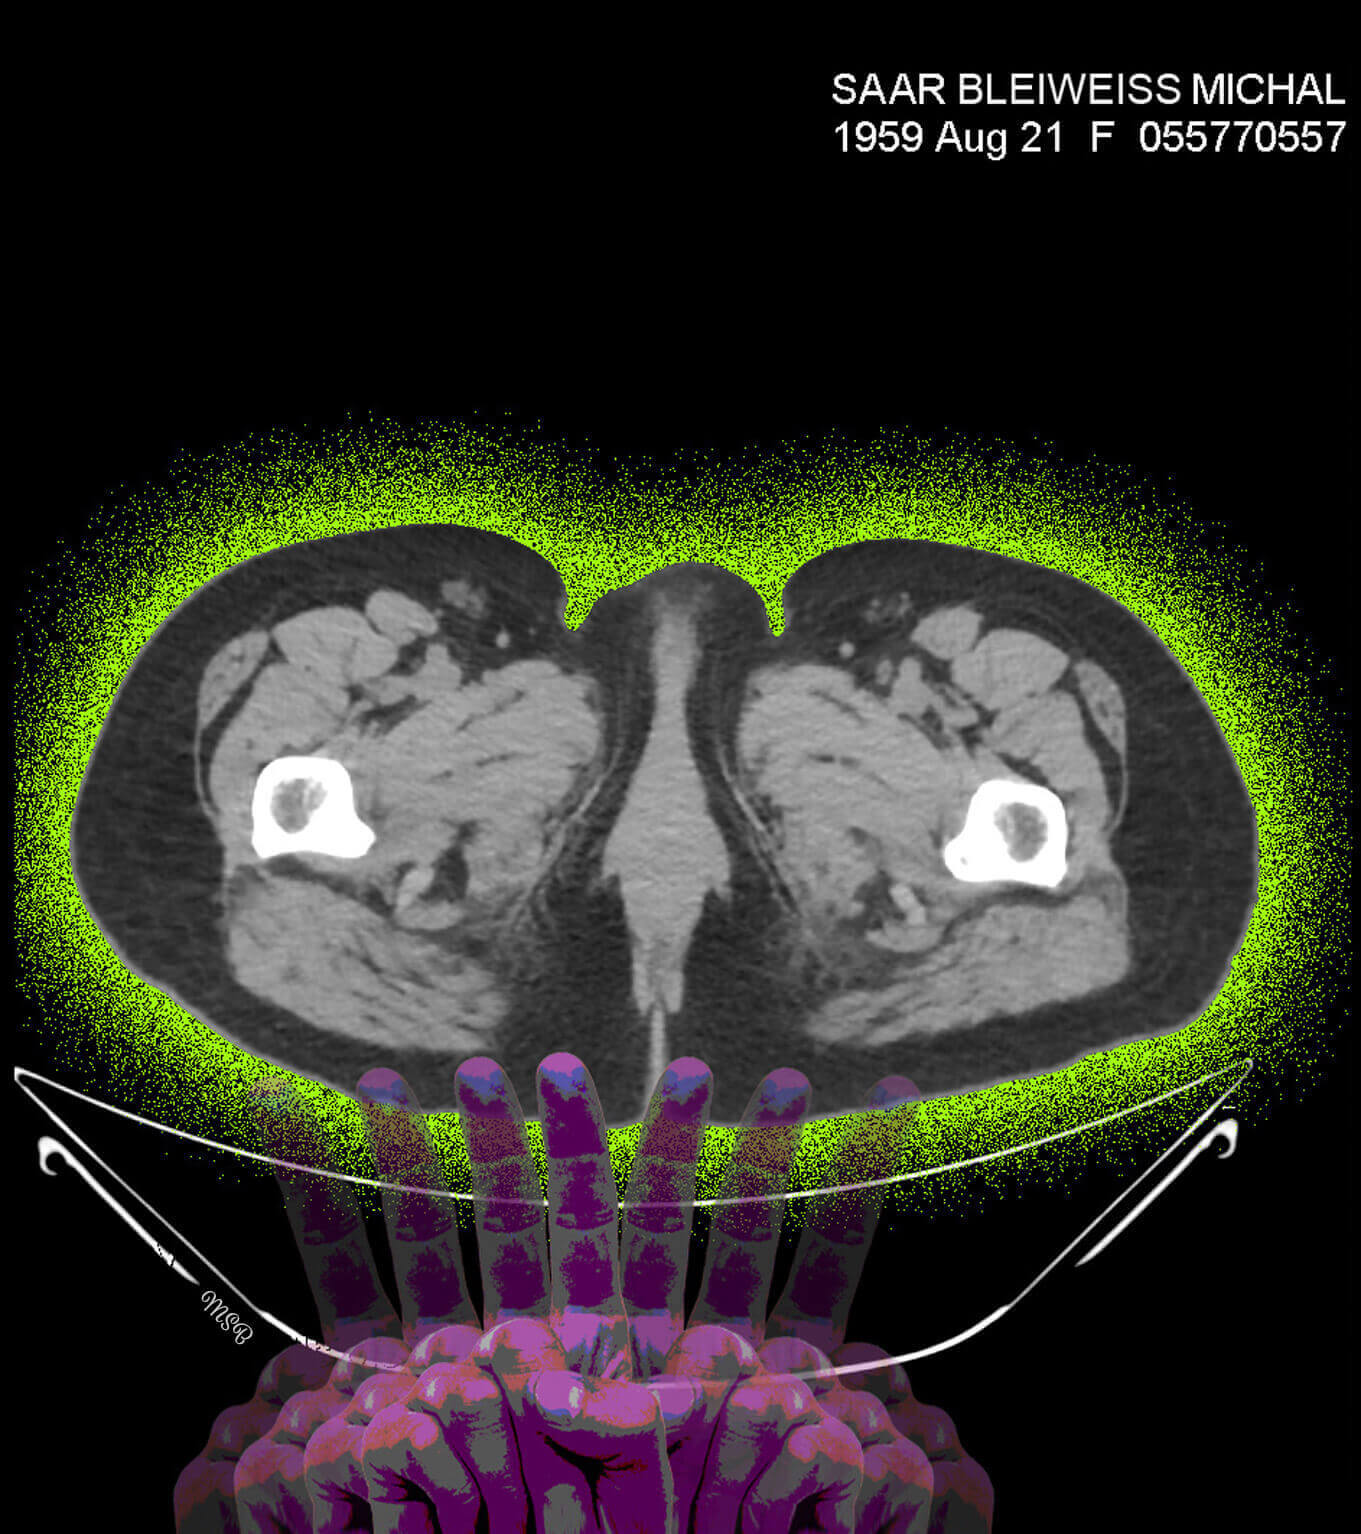

A reimagining of “self,” by Michal Saar-Bleiweiss

A few years ago, I became ill with Nephrostomy and had to undergo surgery. I was sitting with my husband, Mark, at a clinic in Ramat Aviv, Israel, in the office of a professor who specializes in CT* decoding. There, on two huge screens, for the first time I saw my body from the inside, and it was at this moment that my creative impulse arose.

The images before me were entirely in black and white, devoid of personality or character. There was no sign of the Michal that was me, and I felt a great desire and need to take these images to reinstate Michal, the person. When we returned home, I was curious about how I would feel when I looked at the images again—but this time on my computer screen. What I saw created an emotional storm within me.

This storm opened my “third eye,” enabling me to look inside myself. In my imagination I saw colors, dimensions, and expressive features, such as eyes. This was probably my way of internalizing my new reality, digesting what is going on inside me and brushing off my fears and pain. I wanted and needed to wake up each morning with a new smile and the ability to cope.

Mark accompanied me on this journey, and he continues to do so, strengthening me when it is difficult and encouraging me to carry on with my coping mechanisms and my imagination in my inner self.

Having released the pain from the CT images, I found myself opening the next chapter in my imagination—creating digital collages.